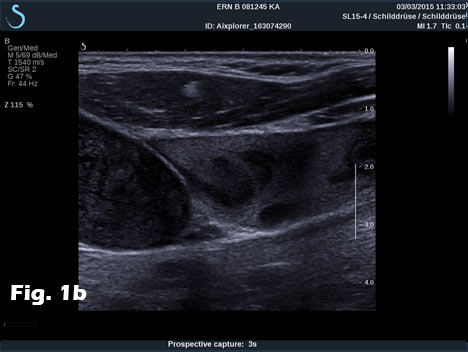

We report on the incidental finding of a 70 y/o patient presenting with an indolent cervical swelling and mass. Clinical examination and laboratory data were not conclusive. In the figure sequence B mode ultrasound and shear wave elastography revealed a 43 mm mass lesion with peripherally stiffer tissue (a) with thrombosis in statu nascendi of jugular vein shown by B mode (b) and also by contrast enhanced ultrasound (c) and shear wave elastography (d). 3D shear wave elastography confirmed the circumscript peripherally stiffer cervical mass (e). 3D SWE added complementary information for a better delineation of the distribution of increased stiffness, following the fibrous capsule around the nerve. SWE also showed feasibility to demonstrate stiffer tissue within jugular vein. 3D techniques allowed improved documentation of the anatomical volume including the tumour and surrounding vessels [(1-3)]. Histologically the nerve tumour schwannoma was proven.

Figure 1:B mode ultrasound and shear wave elastography revealed a 43 mm mass lesion with peripherally stiffer tissue (a) with thrombosis in statu nascendi of jugular vein (b), also shown by contrast enhanced ultrasound (c) and shear wave elastography (d). 3D shear wave elastography confirmed the circumscript peripherally stiffer cervical mass (e).